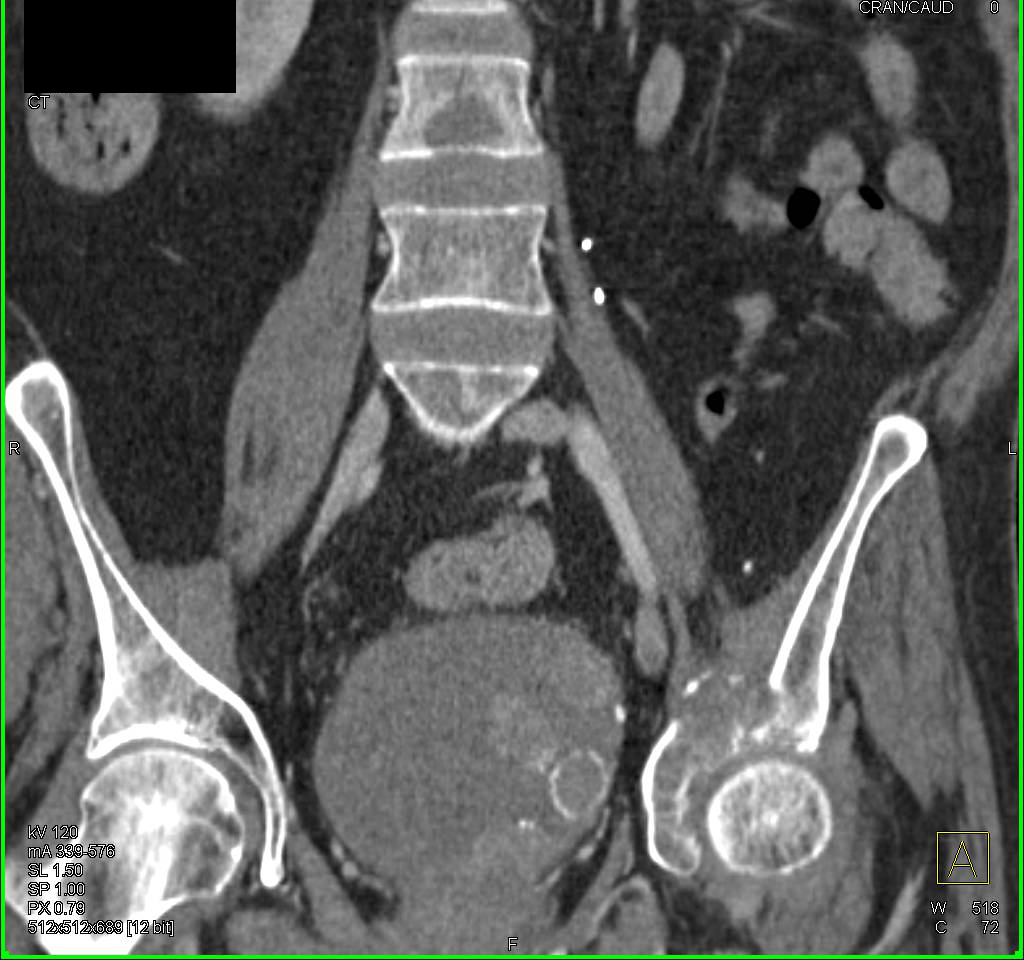

CT scan showing the location of bladder tumor. | Download Scientific …

Urothelial carcinoma of the bladder in a 59-year-old man. CT image …

do ct scan detect early bladder cancer ️ Updated Guide 2022

Bladder cancer CT – wikidoc

Bladder Cancer with CT Urography – Genitourinary Case Studies – CTisus …

CT scan of Case 1: bladder cancer mass with associated left …

CT scan showing bladder wall thickening (arrow) and decrease in tumor …

Bladder Cancer Seen Nicely on Arterial Phase Imaging but also on CT …

Bladder Cancer with CT Urography – Genitourinary Case Studies – CTisus …